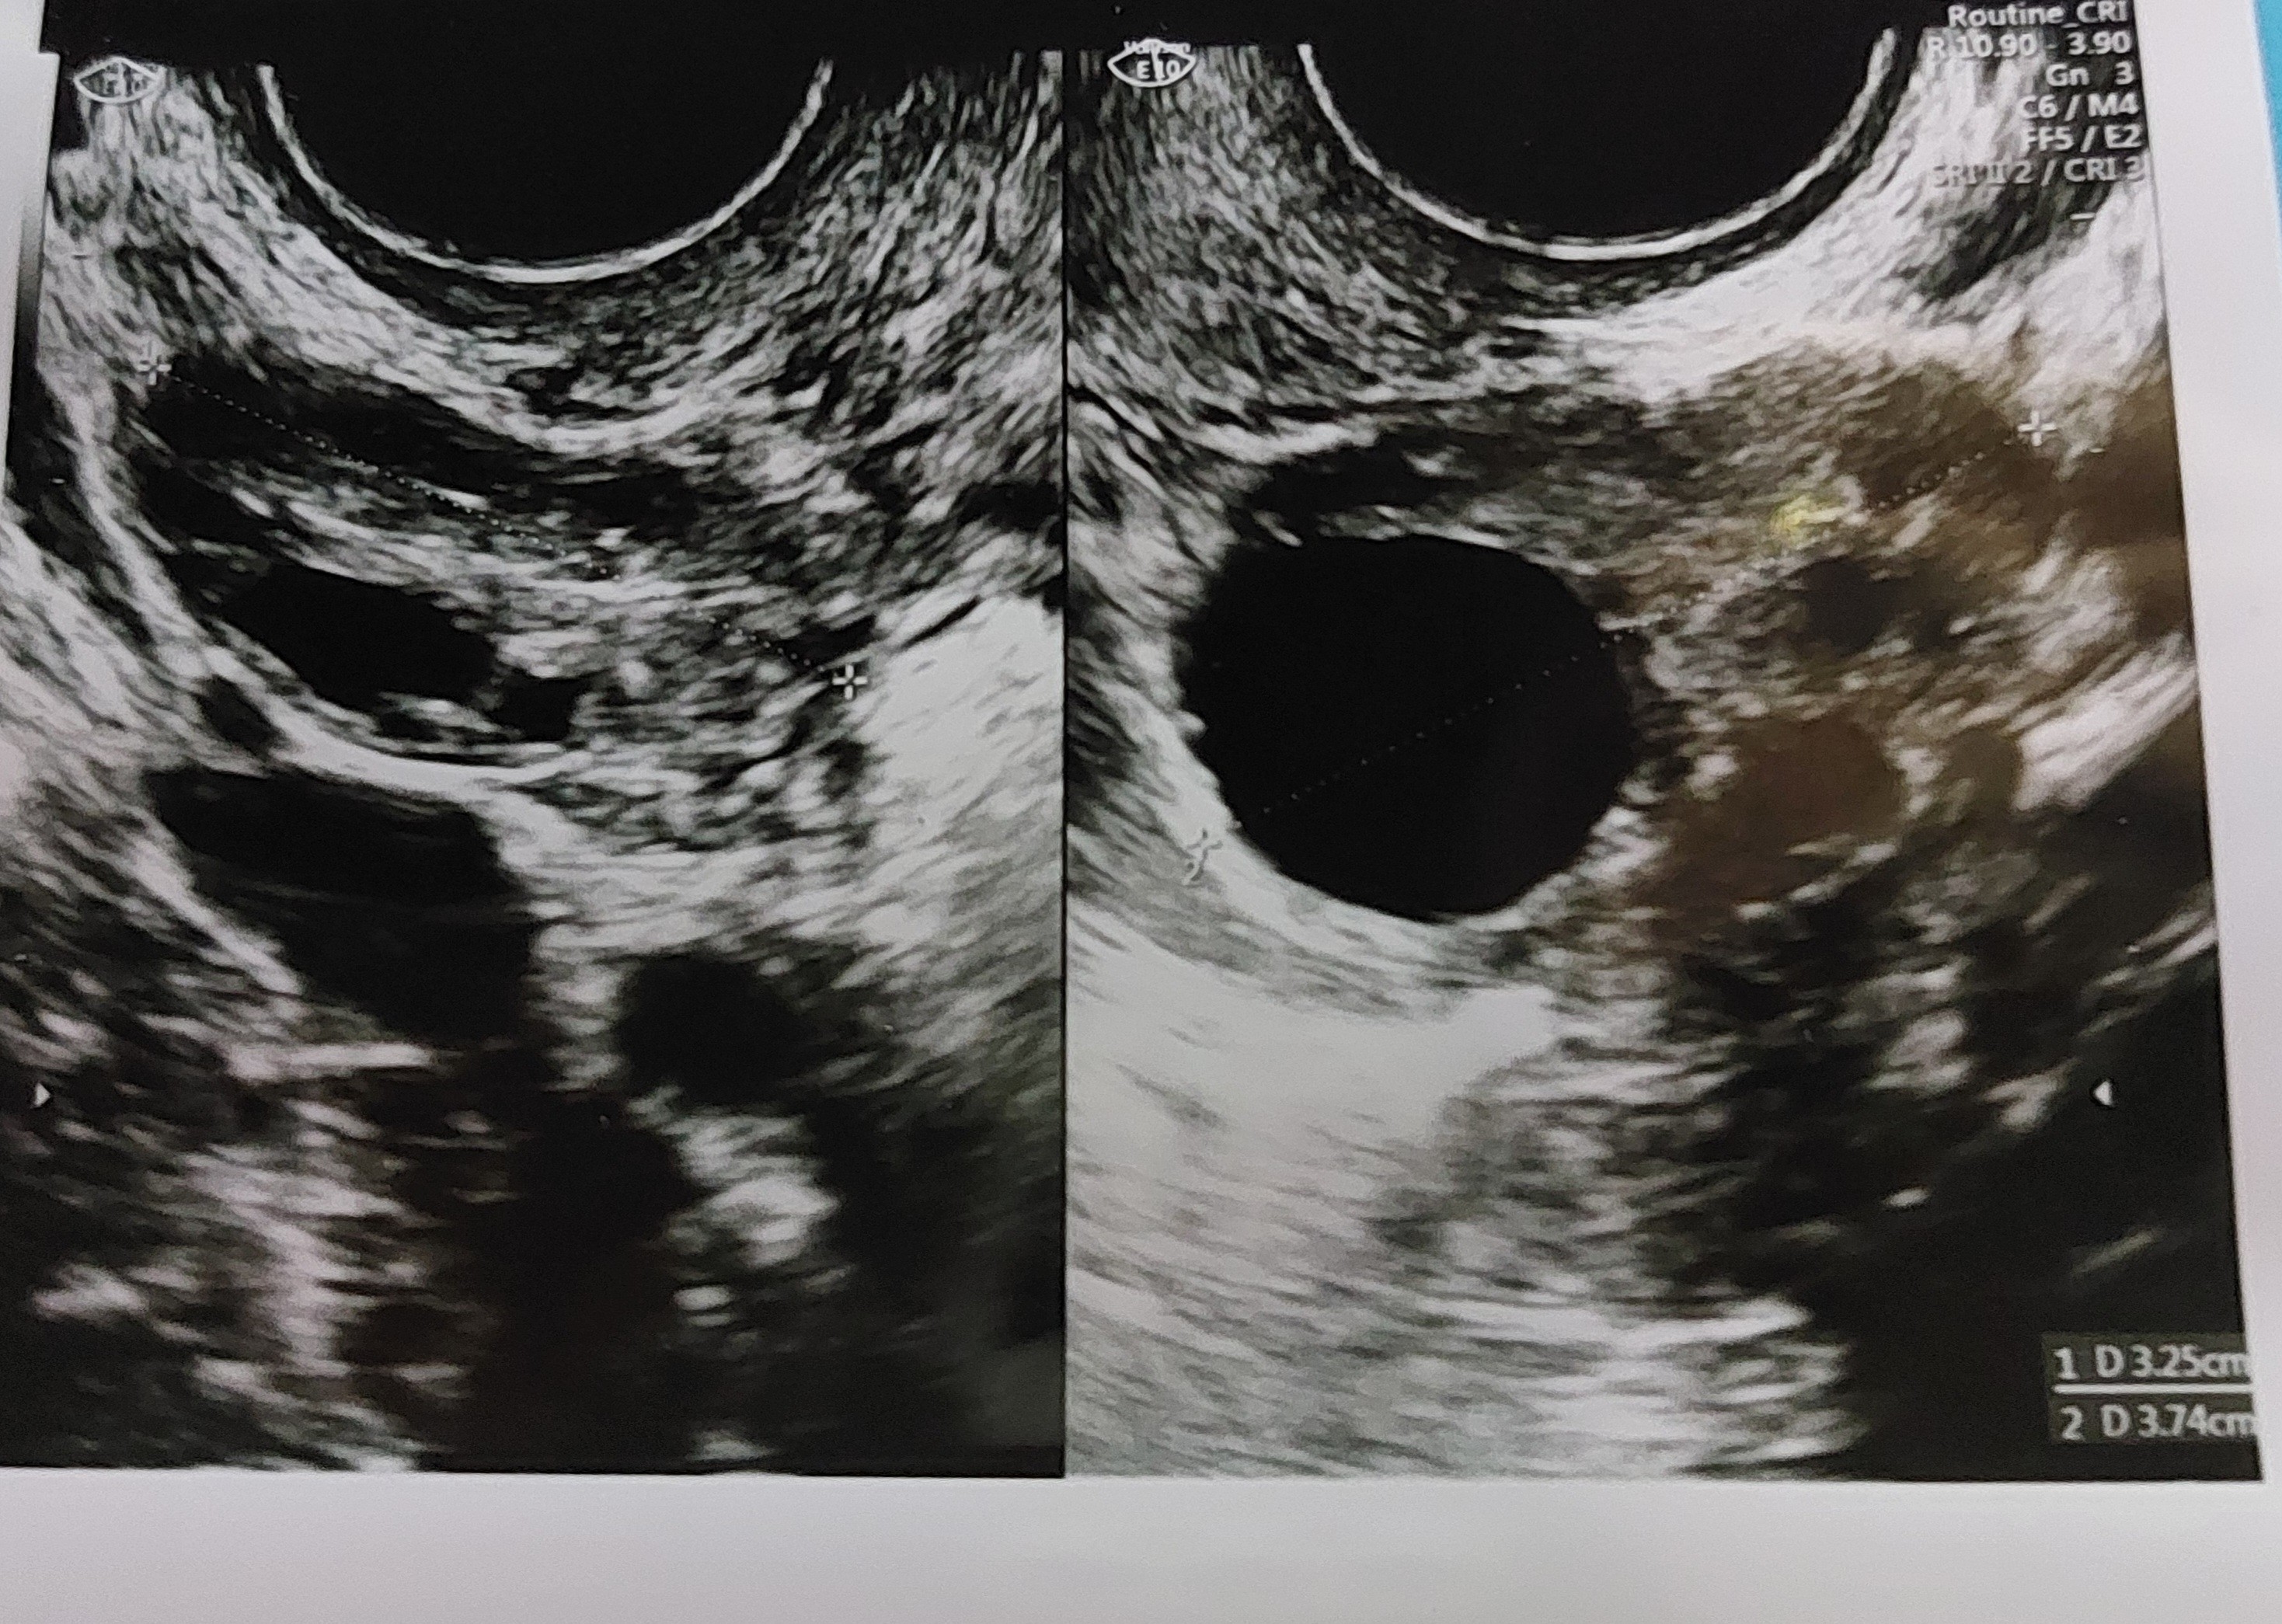

przygotowuje się do owulacji? Tzn ile mm miał pęcherzyk?

Zaczęłam myśleć o tym pęcherzyku i zerknęłam na usg. Wstawię zdjęcie czy tu chodzi o ten pęcherzyk. Bo w sumie co byłam na usg to nikt mi nigdy nie mówił ile ma pęcherzyk. Mam regularne cykle i bywało że byłam na usg w trakcie jajeczkowania, albo przed i po i ta owulacja zawsze była potwierdzona..

• 20241025_194047.jpg

1,3 MB · Wyświetleń: 89

Jak się patrzy na rozmiar pęcherzyka? W necie czytam praktycznie wszędzie o średnicy, że jeśli jest min 18mm to jest już ok itp. A co jeśli kształt jest bardziej nieregularny? Np ostatnio miałam te 14x22 i zastanawiałam się czy to ok, czy powinien być bardziej „okrągły” i coś jest nie tak?

Mój pęcherzyk był ostatnio trójkątny 🤣 Ale doktorowi się spodobał.

U mnie podają zawsze średnicę pęcherzyka. Czasem zwracają uwagę, że jest ładny wzgórek jajonośny, wtedy widać, że okrąg w pewnym momencie wchodzi w taki cypelek.

Mi podaje lekarz zawsze jakiś jeden wymiar tak jak teraz np 2 pęcherzyki po 17 mm